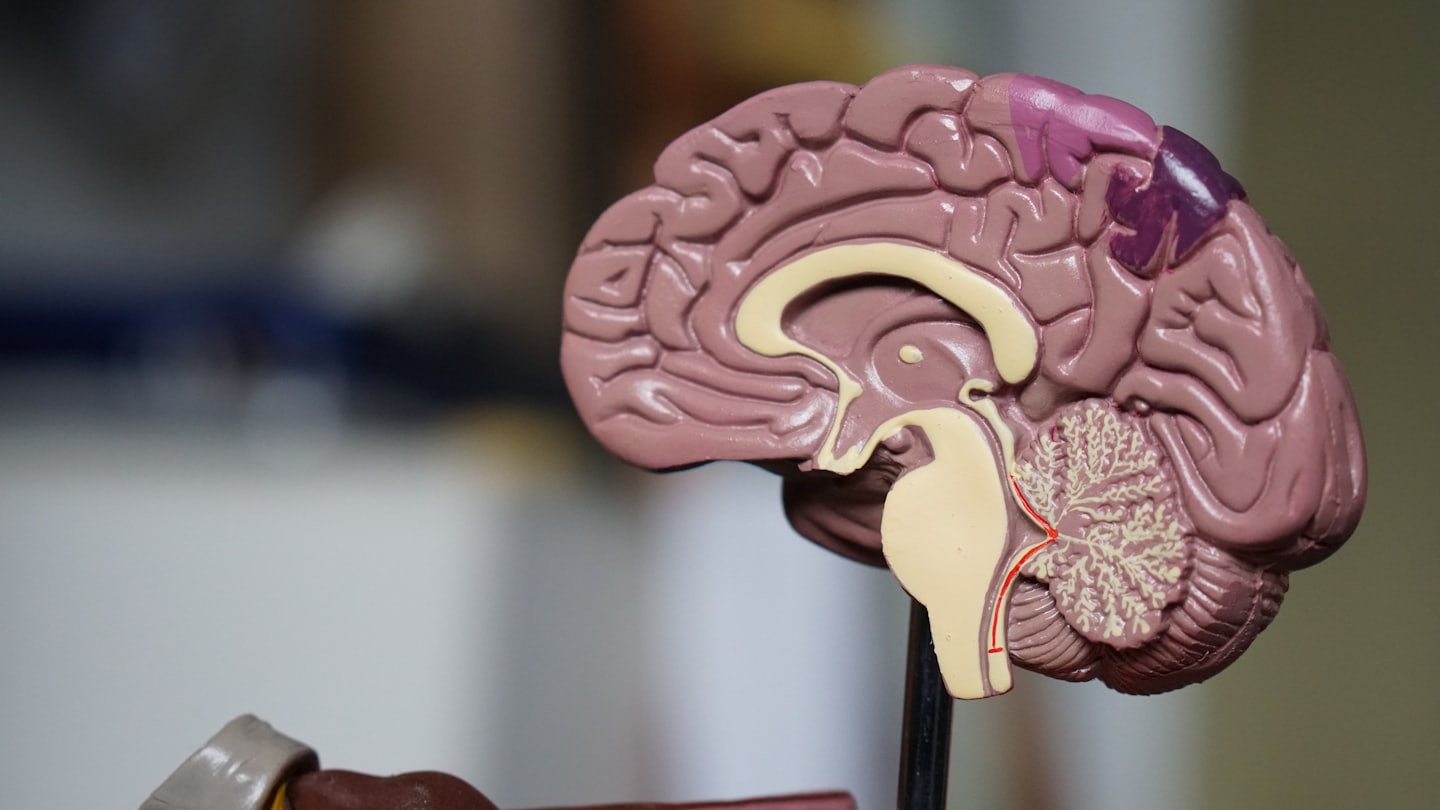

Demencja – podstawy

Poznaj kluczowe informacje, które pozwolą Ci lepiej zrozumieć mechanizmy tego schorzenia.

Jak działa mózg?

Dowiedz się krok po kroku, jak funkcjonuje mózg i jakie działania wspierają jego zdrowie.